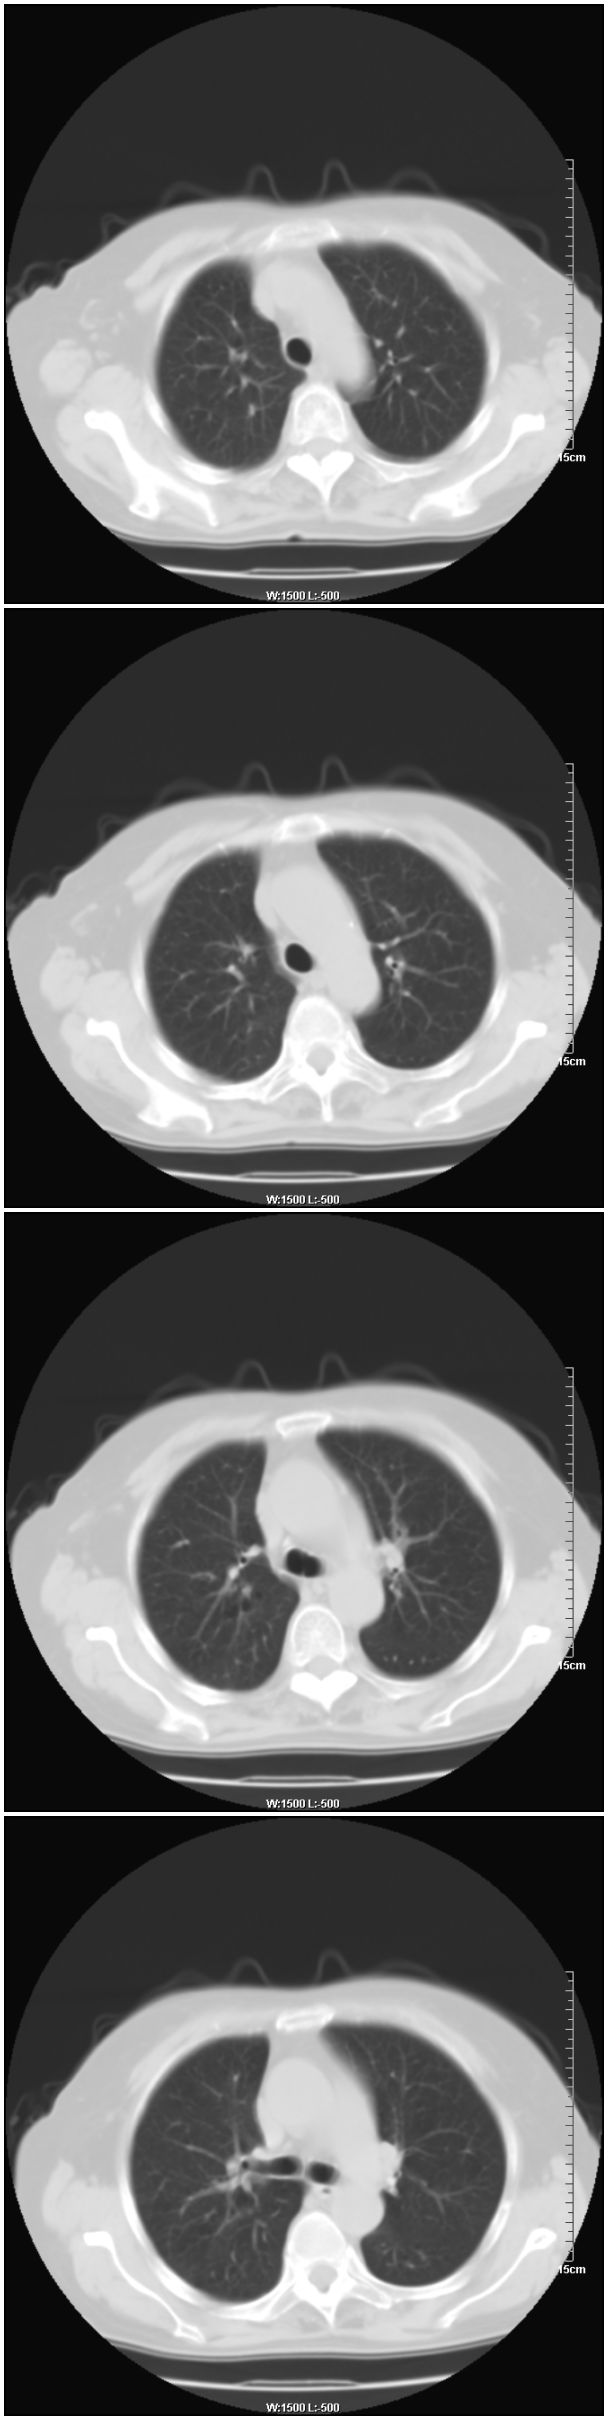

女性,78岁。术前体检发现肺部病变,看看还有什么问题?肺病变是什么性质?

右肺中心型肺癌可能

右肺中心型肺癌可能。支持!

支持!右肺中心型肺癌!

乳腺病变在右侧,右肺门区新生物伴右中叶阻塞性肺炎、部分部张

右肺中叶不规则肿块,管腔阻塞,心包内少量积液,支持右肺中心型肺癌。

应该是右肺中心型肺癌,乳腺的肿物应该在右侧,看见右侧有结节,并乳头凹陷

右侧乳腺内上象限结节影,边缘模糊,右肺病变相邻支气管内见软组织密度影及斑点样钙化灶,考虑肺癌可能性大,建议结合纤支镜检查。

右肺中央型肺癌伴中叶肺不张。